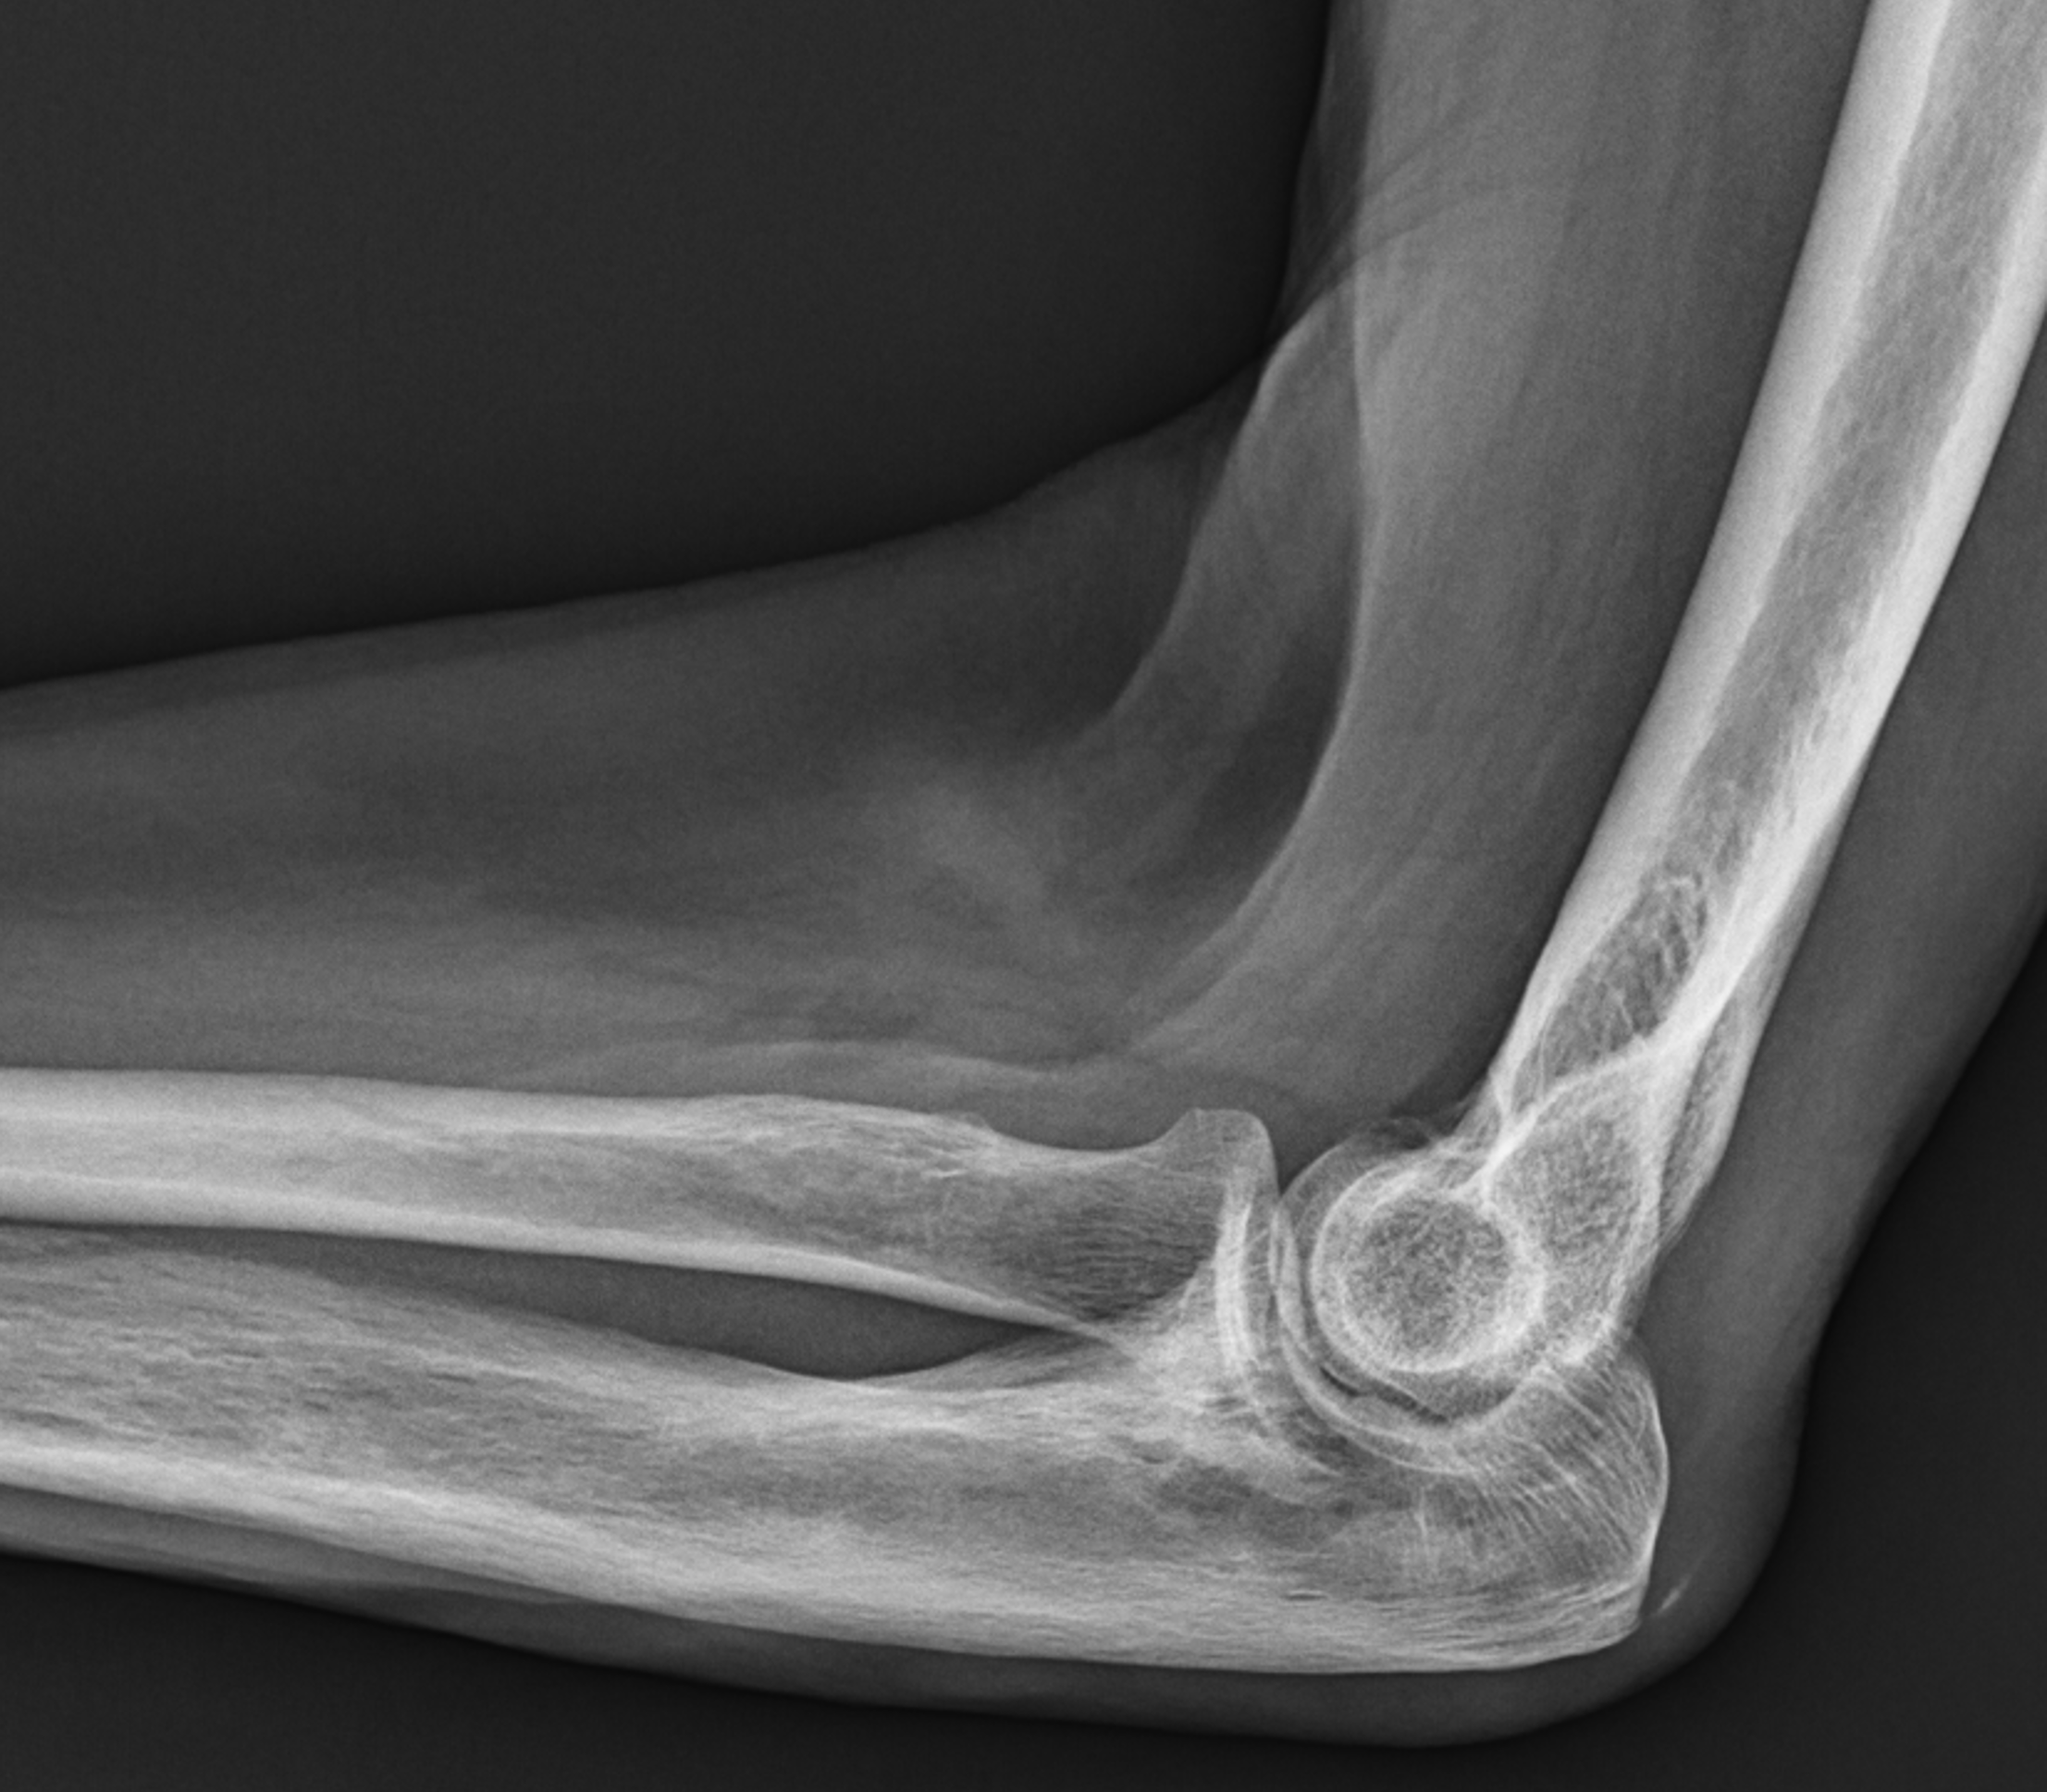

Figure 8: Mixed phase Paget disease in the distal humerus with atypical marrow replacement. (8A) AP and (8B) lateral elbow radiographs show classic findings of Paget disease in the distal humerus, including osseous enlargement, particularly of the medial epicondyle, with associated cortical and trabecular thickening. (8C) T1-weighted and (8D) STIR coronal images show diffusely abnormal marrow signal intensity in the medial humeral epicondyle (asterisks), hypointense compared to skeletal muscle on the T1-weighted sequence and uniformly hyperintense on the STIR sequence. This pattern of marrow replacement is atypical in uncomplicated Paget disease and prompted biopsy, which confirmed the diagnosis. Despite the marrow findings, the radiographic features in addition to the lack of osseous destruction and soft-tissue mass suggest uncomplicated Paget disease and fibrovascular changes. Short interval follow-up to document stability may obviate the need for biopsy in similar cases.